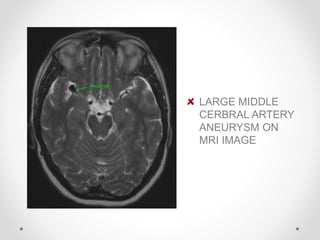

LARGE MIDDLE

CERBRAL ARTERY

ANEURYSM ON

MRI IMAGE